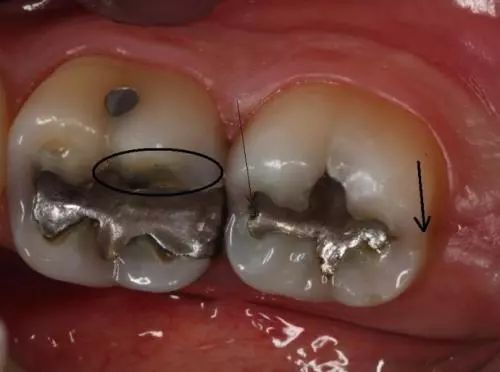

2.牙隐裂——*毒冰**会使服用者感到焦虑、亢奋或紧张,从而导致磨牙。你能看到他们的牙齿上有明显的磨耗痕迹。有时候就算是吃一些很软的食物(如土豆泥),也会使服用者的牙齿出现隐裂。

3.龋齿——*毒冰**成瘾者会因为口干反应而渴望吃含糖量高的食物和饮品。这样,口腔内靠糖类为生的细菌会大量繁殖,并分泌酸性物质,使牙齿损坏更严重。*毒冰**服用者的龋齿通常会从牙龈边缘发展到整个牙齿,前牙首当其冲。

4.牙周病——*毒冰**成瘾者通常不会定期做口腔检查,口腔保健的缺乏会引发牙周病。同时,牙齿和牙龈都需要血液来保持健康,*毒冰**使口腔组织的血管收缩,血流量减少,最终导致口腔组织坏死。

1.吸毒者龋齿发展到牙龈边缘以下。

2.吸毒者牙齿出现缺失。